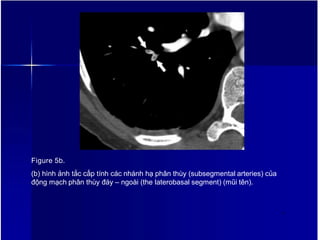

Figure 5b.

(b) hình ảnh tắc cấp tính các nhánh hạ phân thùy (subsegmental arteries) của

động mạch phân thùy đáy – ngoài (the laterobasal segment) (mũi tên).